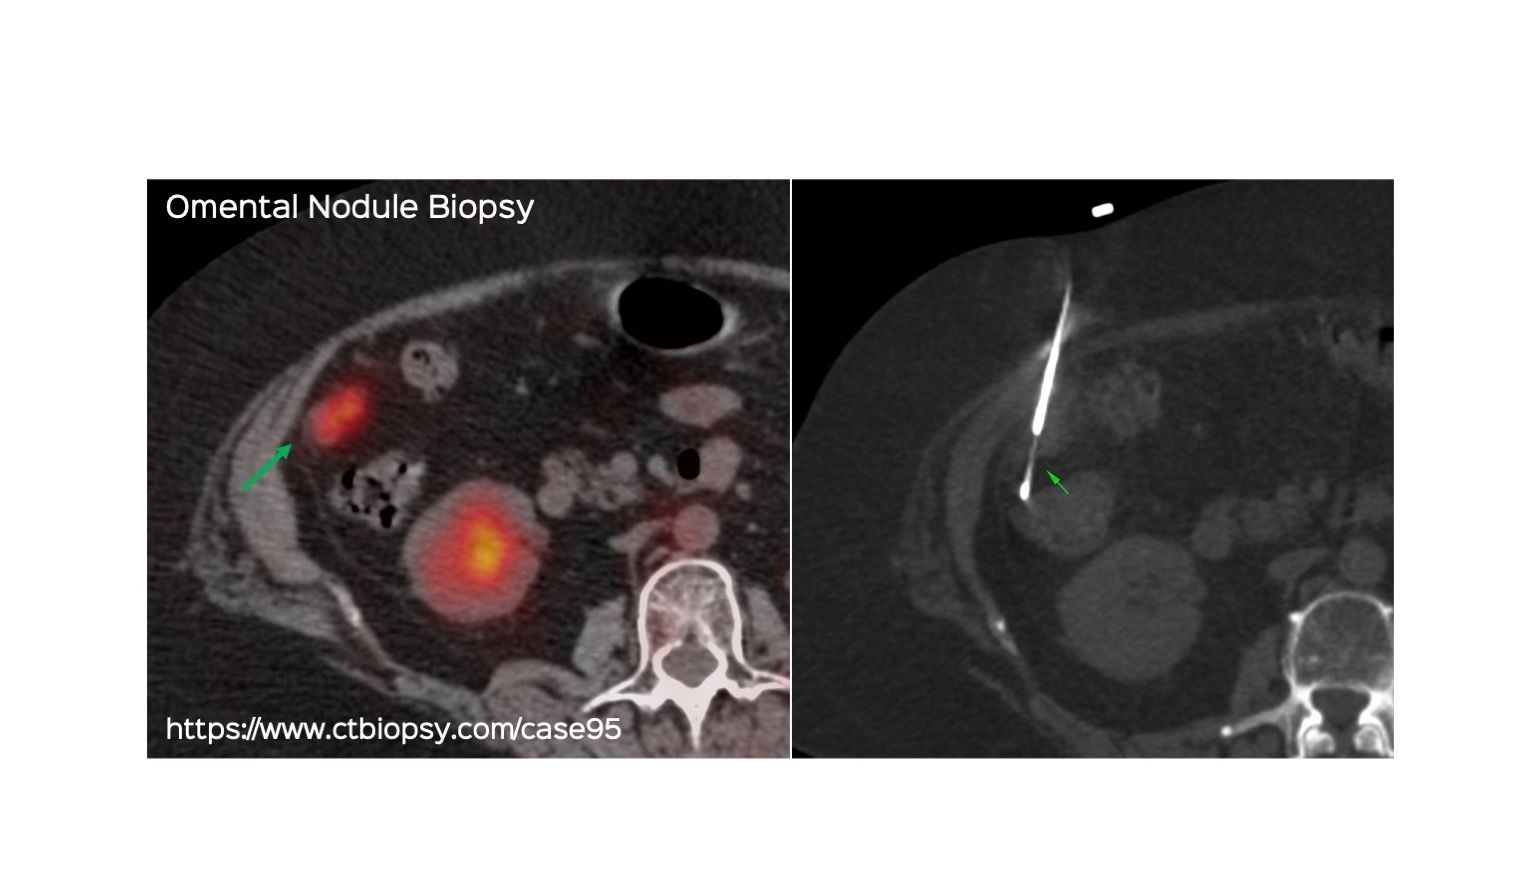

Case 95: Omental Nodule Biopsy